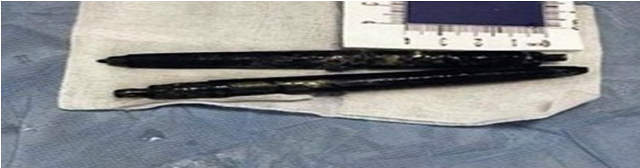

Jednom 50-godišnjem Kinezu punih 36 godina u stomaku “skrivale” su se dvije hemijske olovke.

Wang je kao tinejdžer izgubio opkladu od prijatelja dok su pili, a zbog izgubljene opklade tada mladi Wang morao je progutati dvije plastične hemijske olovke.

Nakon 36 godina ljekari iz grada Suzhou napokon su uklonili dvije olovke koje su se dugi niz godina “skrivale” u njegovom stomaku nakon izgubljene opklade a fotografije su sada i zvanično objavljene na internetu.

Olovke su toliko dugo godina bile u njegovom stomaku zbog činjenice da ih je i sam Wang vremenom zaboravio, misleći kako ih je njegovo tijelo izbacilo jer nije imao nikakvih zdravstvenih problema tokom svih ovih godina.

Ipak, kada je u februaru ove godine obavio rendgensko snimanje stomaka, ljekari su ostali šokirani onim što su ugledali. Hirurzi navode da su olovke bile iznenađujućem dobrom stanju s obzirom da su izdržale 36 godina želučanih kiselina.

Hemijske su izvadili na kraju izvadili operacijom, a ostalo je nepoznato da li se moglo još uvijek s njima pisati.